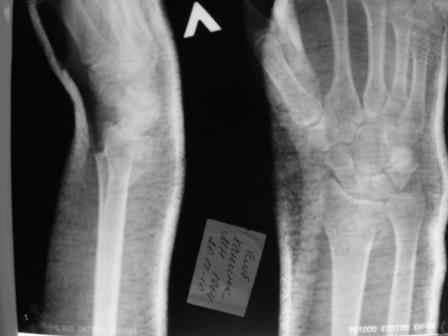

Уважаемые коллеги.Прошу обсудить случай лечения перелома дистального метаэпифиза лучевой кости. Ситуация скандальная и крайне неблагоприятная. Больная с патологической обстоятельностью мышления, склонностью к сутяжничеству, патологическими умозаключениями, не поддающимися коррекции (см. психиатрию, правда офиц. диагноза нет). В данном случае есть ряд ошибок с нашей стороны, прежде всего в отношении качества ведения документации (за что получил административное взыскание, по делом мне дураку). В остальном- придерживались в лечении подхода классический советской школы. Так как умную операцию…… сами знаете… 15.12- перелом луча в Москве. Там же репозиция, гипс. Дальнейшее лечение у нас в ЦРБ. 20.12.- вторичное смещение в гипсе21.12- под внутривенным наркозом- репозиция, гипсовая лонгета. Дальше начинается самое интересное. После репозиции больная заявила, что я (репозицию делал я) порвал ей все связки в суставе, посинел у нее 5 палец, якобы я за него тянул и т. д. На самом деле на 2 сутки после репозиции рука немного отекла и было незначительное сдавление гипсом, который был ослаблен. Дальнейшее лечение консервативное. Через 6 недель- гипс снят, назначено ЛФК. Пациентка крайне недовольна. Говорит, что на снимке у нее выступает кость, я ей сломал руку и.т.д. В общем началось. Пациентка прочитала в интернете наверное все, что есть по данной травме.По заключениями рентгенологов и консультанта из КДЦ областной больницы - стояние отломков допустимое. Объективно говоря- снижена высота лучевой кости, диастаз лучелоктевого сочленения, и не сросся шиловидный отросток. однако на РКТ при сравнении с другой стороной- разница незначительная. Дальше в одной из больниц нашей области и одной из больниц Москвы (вроде бы КГБ 53) врачи сказали, что репозиция сделана плохо. Нужна операция (восстановить длину лучевой кости), даже один из них предложил РЕДРЕССАЦИЮ (хи-хи) с наложением аппарата Илизарова. Что это для данной больной- радость неописанная. (см. описание психического статуса). Ничем другим, кроме зарабатывания дешевого авторитета объяснить данный факт не могу.Кстати, у больной еще нейропатия локтевого нерва.Для разрешения конфликта больная направлена на консультацию в ЦИТО на 03.03.11.

Заключение: Консолидированный в неправильном положении перелом дистального метафиза левой лучевой кости. Ротационная контрактура левого предплечья. Рекомендовано- разработка, консультация через 2 месяца.

Объективно: пронация почти полная, супинация ограничена, ладонная флексия около 20, тыльная 10. Гипостезия в зоне инервации локтевого нерва. Незначительный отек. Хват кисти полный. Сила 4 балла.

В общем, типичная картина раннего восстановительного периода после снятия гипса. Визуально конечность не изменена.

Мне кажется, что на самом деле, ситуация не стоит и выеденного яйца. При правильном лечении должно быть полное восстановление функции.